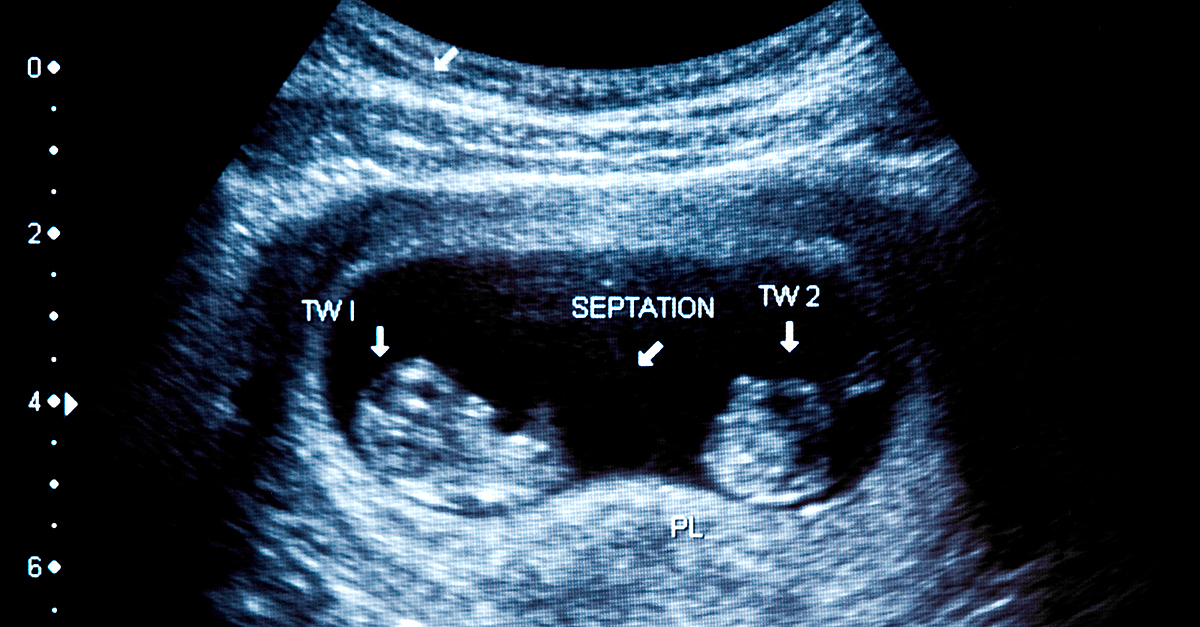

Crystal Murphy, M.S., CNM, APRN, explained that, unfortunately, there really isn't a way to predict whether Vanishing Twin Syndrome will happen—instead, it becomes apparent when a follow-up ultrasound reveals that one of the previously detected embryonic sacs of the pregnancy has gone missing.

"Initially, on ultrasound we see two embryonic sacs," said Murphy, who works as a midwife at Tru Birth Center in Lakewood, New Jersey. "Then, when you go back at the next ultrasound, there is no longer two of them—it's down to a single pregnancy."